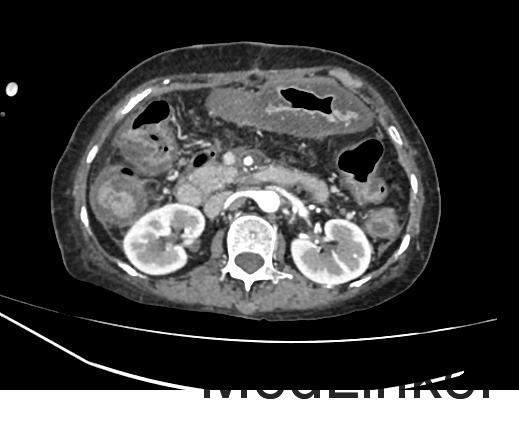

患者女,72岁,主因“消瘦半年,查体发现胰腺肿物1月”入院;患者半年前开始无明显诱因出现消瘦,体重逐渐减轻,约有3Kg。肿瘤标志物检查:癌胚抗原和CA-199增高。腹部CT平扫和腹部CT增强检查示:胰腺颈部肿瘤性病变,考虑胰腺癌可能性大。现为进一步诊治收入我科。

查体:无异常。 辅助检查:肿瘤标志物;癌胚抗原7.82ng/ml↑,CA-199197,60U/ml↑。 腹盆CT平扫;1、胰腺颈部不规则低密度影,占位性病变待除外,建议增强CT检查。 腹部CT增强;1、胰腺颈部肿瘤性病变,考虑胰腺癌可能性大,建议进一步检查。

诊断:1.胰腺肿物 胰腺癌 治疗:腹腔镜探查、转开腹胰体尾+脾切除术(术中冰冻病理提示胰腺癌)